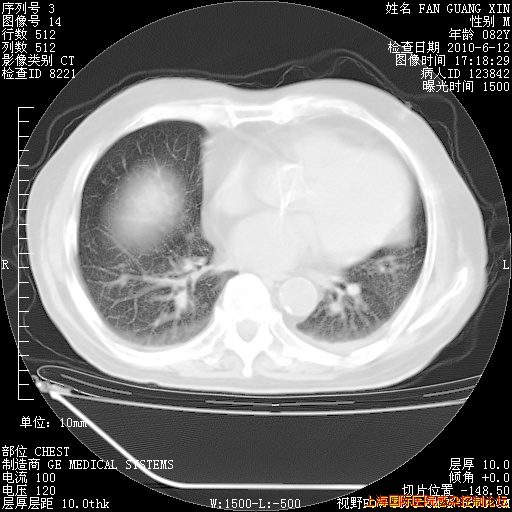

6月12日纵膈窗

整整相隔30天的肺部CT好像有所好转啊。甲强龙减量第3天,需要观察体温。

海管,自昨日你和我通完话后,不知您岳父消化道症状有无缓解?体温怎样?阅读7.12日胸部ct,个人认为目前激素治疗是有效的,甲强龙减量是适宜的。因在抗痨治疗,需密切观察肝功、肾功能和血常规。不过,老年、长期住院和大量使用激素,很担心菌群失调发生